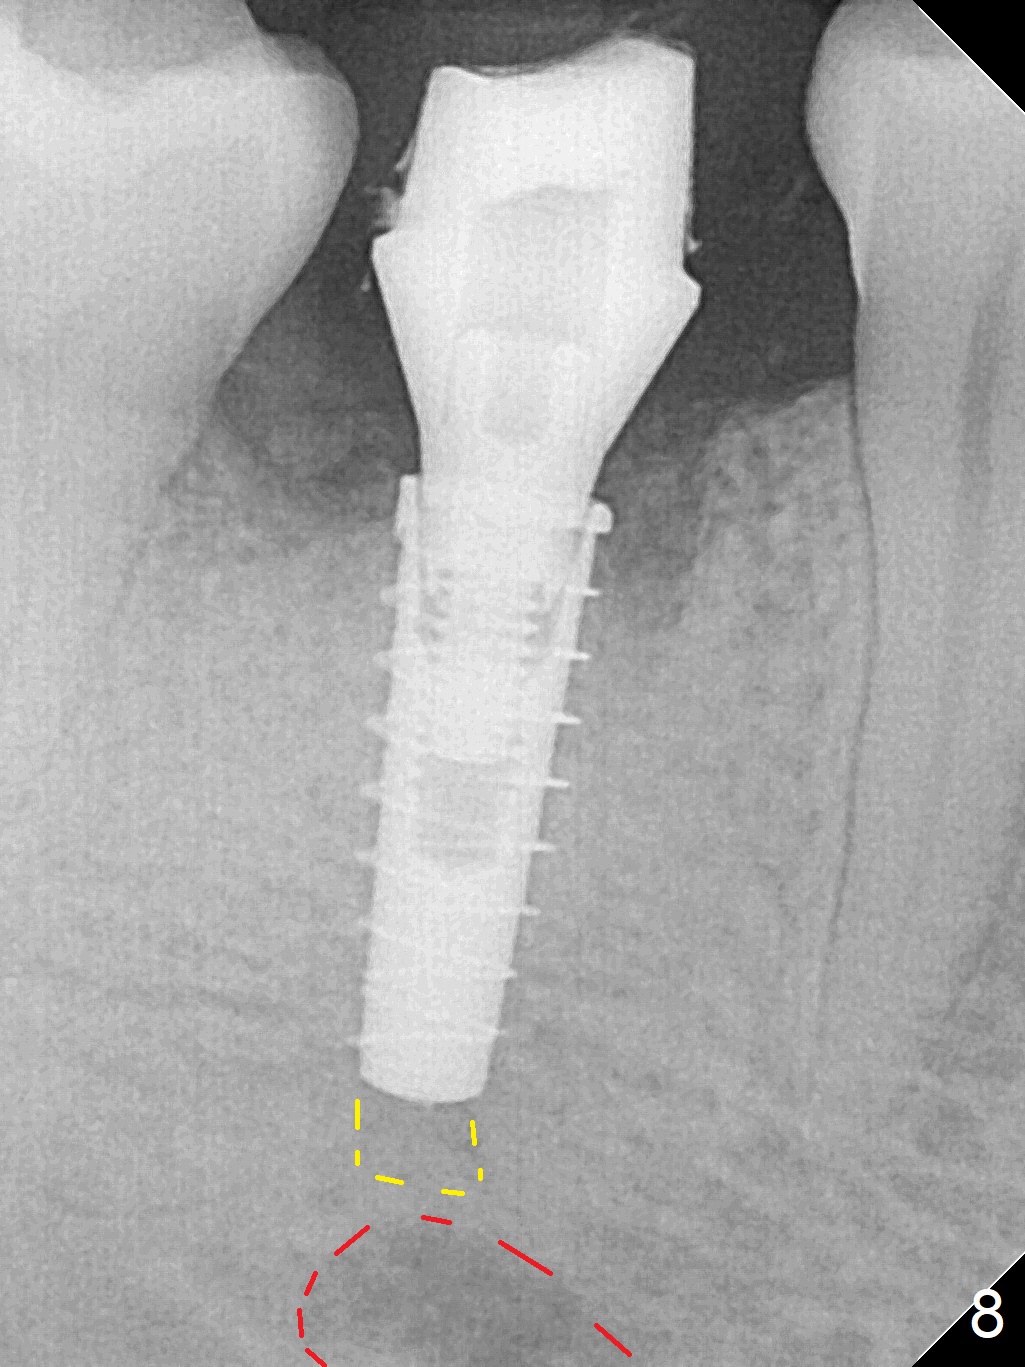

The lower 2nd primary molar has buccal furca lesion (Fig.1 *) with the thin buccal plate (Fig.2). Osteotomy is initiated in the sloped septum (Fig.3). After use of Magic Drill (MD) 3.3 mm for 13 mm and MD 3.8 mm for 11 mm, placement of a 4x11 mm IBS implant meets resistance because of the dense bone (Fig.4-6, red dashed line: Mental Loop) with final insertion torque >50 Ncm. After placement of a 6x4(3) mm abutment and autogenous bone in the remaining shallow sockets (Fig.6), a provisional is fabricated (Fig.7). Finally periodontal dressing is applied. Impression is taken 3 months postop (Fig.8). Buccal infection develops 2 weeks post cementation (Fig.9). When the crown/abutment is removed, there is no residual cement. The implant threads can be felt through the fistula. After soft tissue debridement and copious irrigation, Arestin is placed in the fistula. The latter disappears 15 days post debridement. The patient feels better and moves out of state. It appears that early periimplantitis develops because of the preexisting buccal furca lesion and failure to place the implant deep. The implant will be placed deep after loosening a little (since there is apical space (Fig.8 white line)) or removed, truncated at the apex and placed lower than the buccal crest.